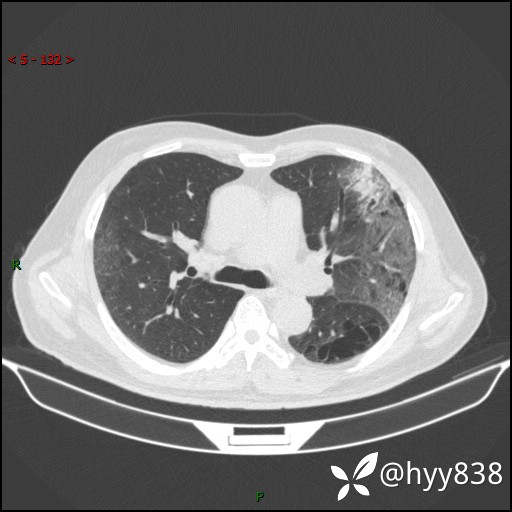

一周后胸部CT